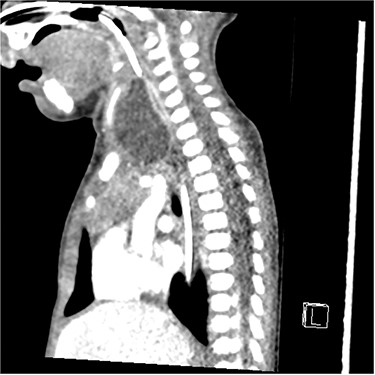

Sagittal barium sallow illustrating the presence of an oesophageal diverticulum, filled with contrast on swallowing.

At age 8 months, the patient was admitted to hospital from clinic due to worsening stridor. She underwent a further MLB that once again illustrated a cyst. An ultrasound scan was performed intraoperatively to aid with emptying of the cyst, and an incidental finding of a connection between the cyst and the cricopharyngeal region was identified, in keeping with a diagnosis of an oesophageal diverticulum. This was later confirmed on a barium swallow study (Fig. 4). Following the MLB, the patient remained clinically stable; the stridor resolved.